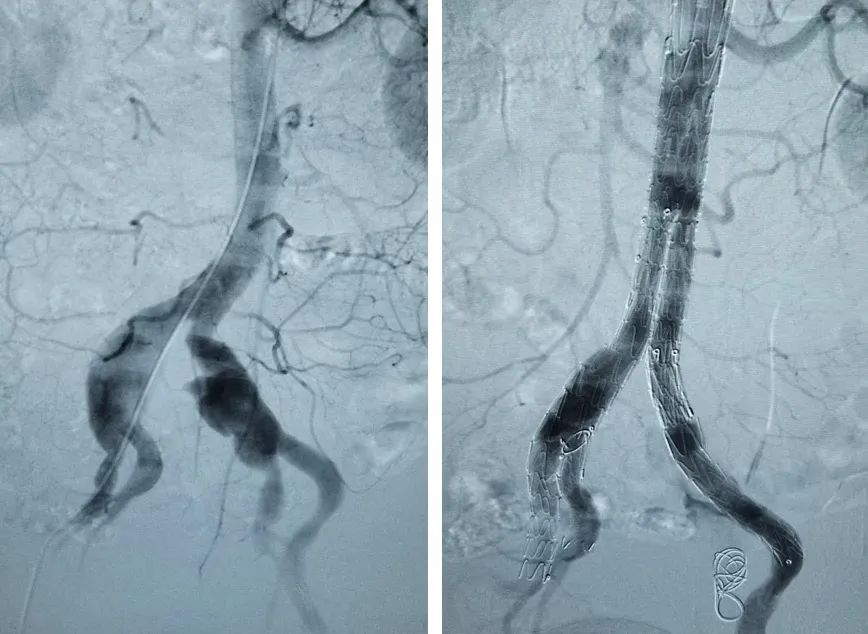

术前及术后DSA造影

CTA示双髂动脉瘤

髂内动脉分支支架